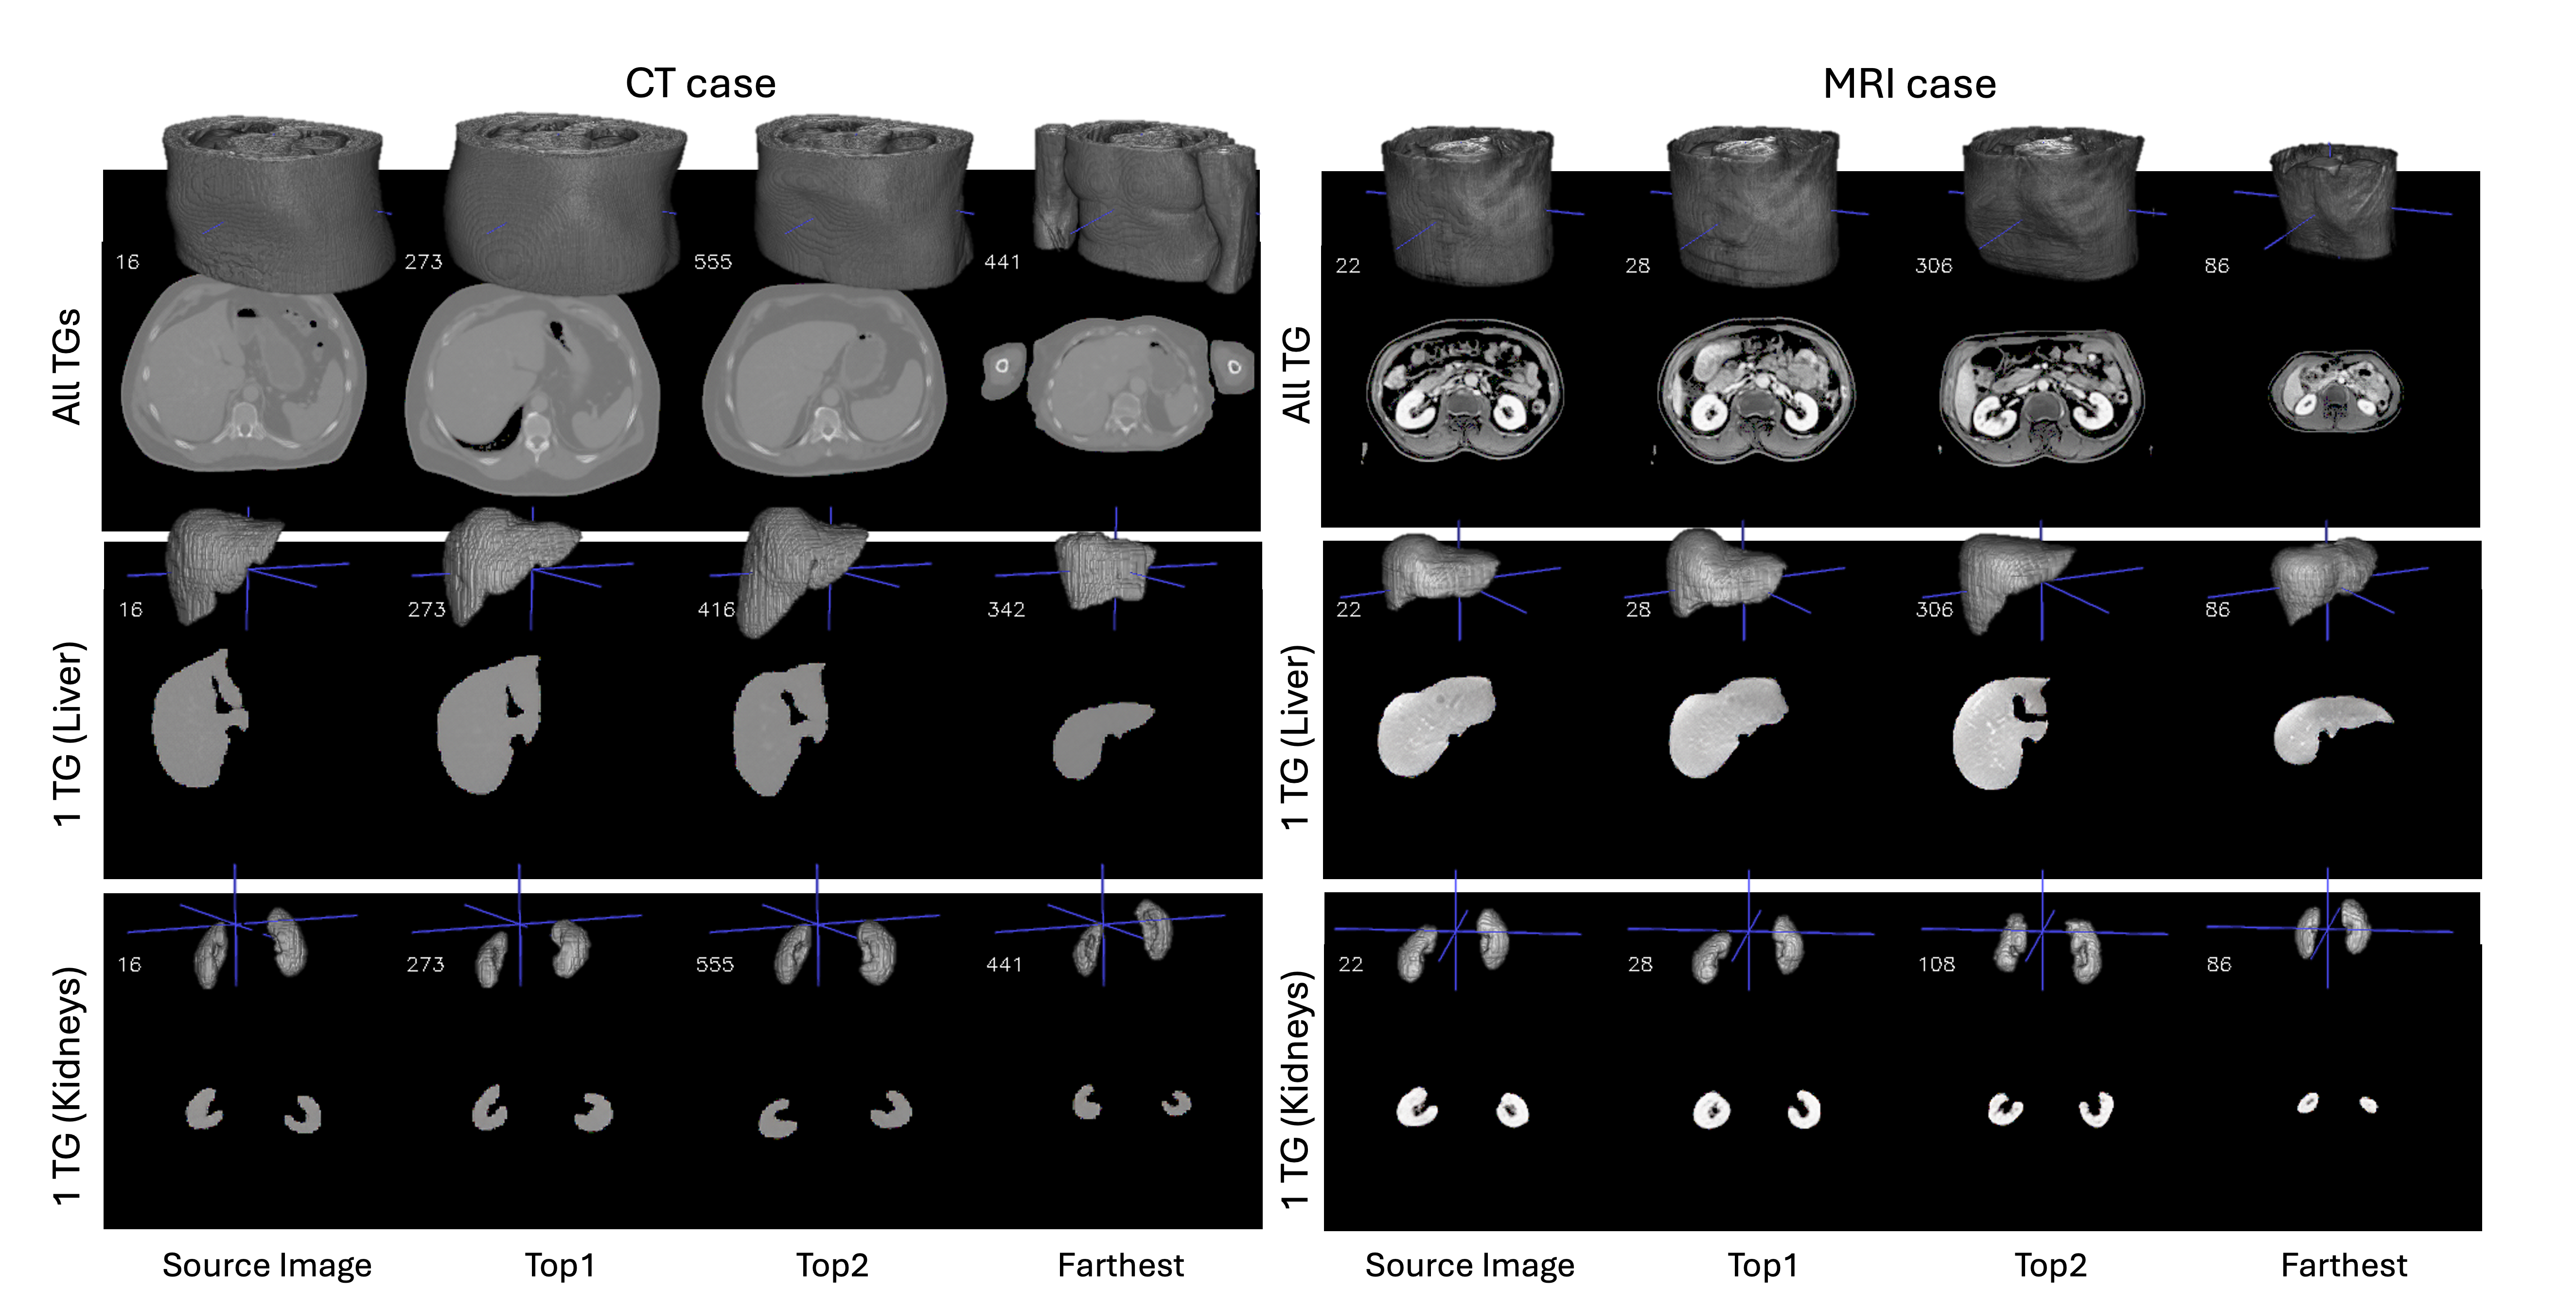

Refer to caption

Figure 5: Semantic-based retrieval of CT/MRI images.

Due to the semantic independence of the token group, Fig. 5 shows that our approach not only supports holistic-level retrieval, but also enables organ-level retrieval (L2L_{2} distance measure). Specifically, we demonstrate top-1, top-2, and maximum-distance retrieval results on both CT and MRI modalities for different token groups. The case indices in the top-left corner of each row indicate how retrieval results vary for different organs of interest. Since experiments in reconstruction and segmentation demonstrate that each token group preserves both the spatial structure and texture details of its corresponding organ, this organ-specific retrieval can be highly beneficial in medical scenarios. For example, it can help radiologists quickly locate similar organ regions across multiple patients, facilitate region-based comparisons of pathology progression, or assist in reference image selection for organ-specific diagnoses.